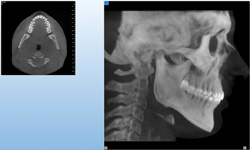

3D DVT - NewTom

Je speciální zubní digitální tříprostorový tomograf (3D), který umožňuje na základě jediného

snímkování vytvořit všechny typy RTG zobrazení, které jsou pro lékaře potřebné. Díky používané technologii tzv. „kuželového paprsku“ a speciálním senzorům je

výrazně zmenšená dávka záření - o více jak 80% proti klasickému CT vyšetření. To je významné zejména u dětí. Pomocí tohoto přístroje je možné zjisti skutečnou situaci v čelistních kostech pacienta tedy množství kosti - můžeme změřit skutečnou šířku i výšku kosti, i kvalitu kosti (hustotu) v místě uvažované implantace. 3D (tříprostorové) zobrazení umožňuje zvýšit prostorovou představu operatéra ještě před vlastní operací a zároveň pacientovi lépe objasnit a ukázat oblast plánovaného zavedení implantátu.

Pacient „neumí číst“ RTG snímky, ale díky 3D zobrazení vidí „svoji skutečnou čelist“

- např. jak je nízká či úzká, vidí průběh nervu nebo velikost čelistní dutiny, což mu umožní i pochopení nutnosti v některých případech provést pomocné zákroky ještě před vlastním zavedením implantátu (viz. kostní štěp, sinus lift, kostní granulát...).

Vyšetření pomocí tohoto přístroje používáme i ve stomatochirurgii (zlomeniny čelistí, zuby moudrosti, cysty, onemocnění čelistního kloubu), ortodoncii (retinované zuby, nadpočetné zuby), parodontologii atd.